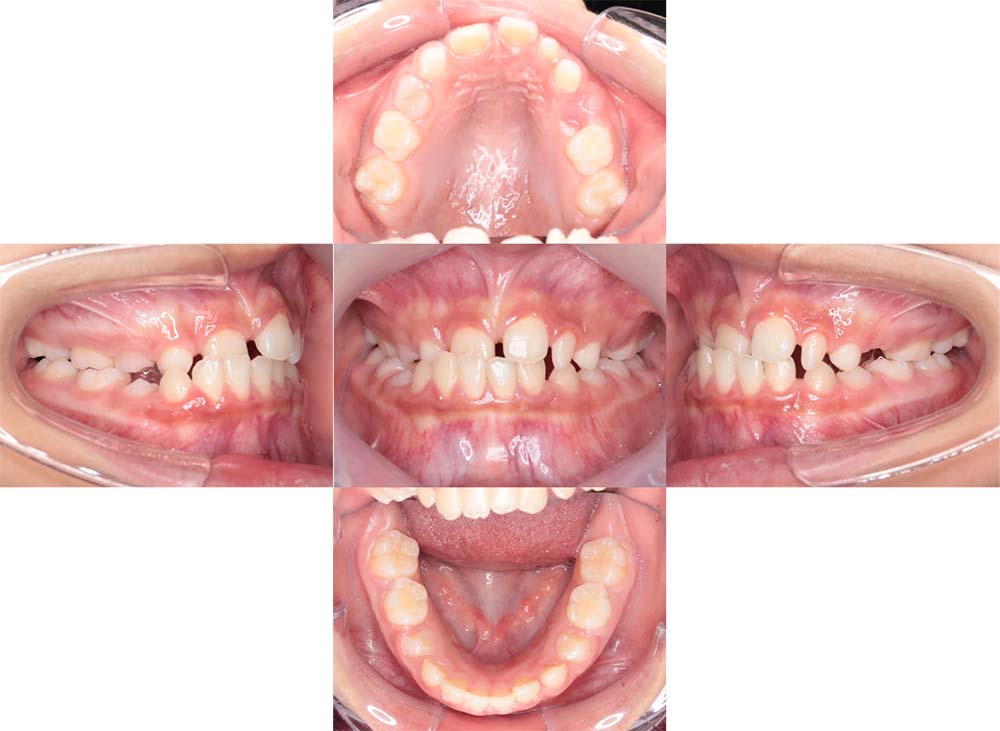

症例02

| 主訴 | 下あご顎が出ている。曲がっている。 |

| 診断名あるいは主な症状 | 反対咬合、非対称、空隙歯列、過蓋咬合 |

| 年齢/性別 | 19歳・女性 |

| 矯正ステージ | 大人の矯正治療 |

| 治療方法 | ワイヤー矯正、顎矯正手術の施行 |

| 抜歯部位/抜歯有無 | 非抜歯 |

| 治療内容 | 上下顎歯列を並べた後に顎矯正手術の施行。 |

| 費用 | 保険治療 |

| 治療期間 | 3年2ヶ月 |

| 主なリスク・副作用 | 痛み、歯根吸収、歯肉退縮、虫歯、後戻り |